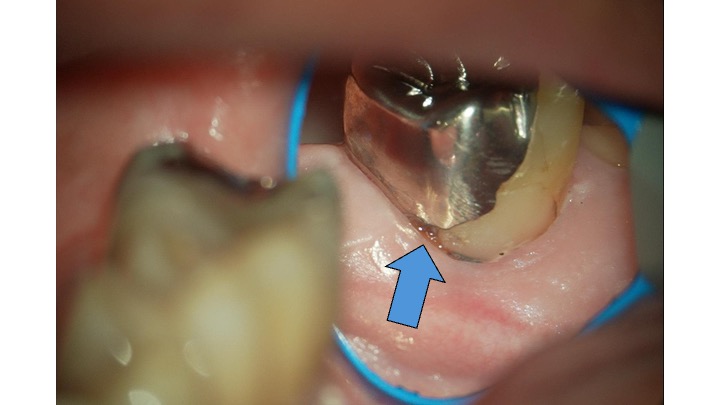

1. 「外注」による適合精度の限界 当院を含め、多くの歯科医院では、保険の銀歯(パラ)の製作を外部の歯科技工所に依頼(外注)しています。 保険診療には決められた材料費と技術料の枠組みがあります。歯科技工所はその限られたコストの中で製作し経営していかなければならず、どうしても「短時間で多くの数を作る」必要があります。 熟練の歯科技工士さんであっても、保険のルール内では「ミクロン単位の精密な調整」に時間をかけることは物理的に不可能です。その結果、どうしても歯と金属の間にわずかな「隙間」や「段差」が生じやすくなってしまうのです。

1. マイクロスコープによる精密な形成(削り出し) 詰め物をピッタリ合わせるためには、土台となる歯の形が滑らかでなければなりません。 当院では、マイクロスコープを用いて、ミクロン単位で歯の形を整えます。

3. 院内技工士との密な連携 当院には3名の歯科技工士が常駐しており、自費の詰め物は院内で、マイクロスコープを使って精密に作製します。 「数をこなす」必要がないため、一人の患者様の歯にじっくりと丁寧に向き合い、顕微鏡レベルでの適合を追求できます。